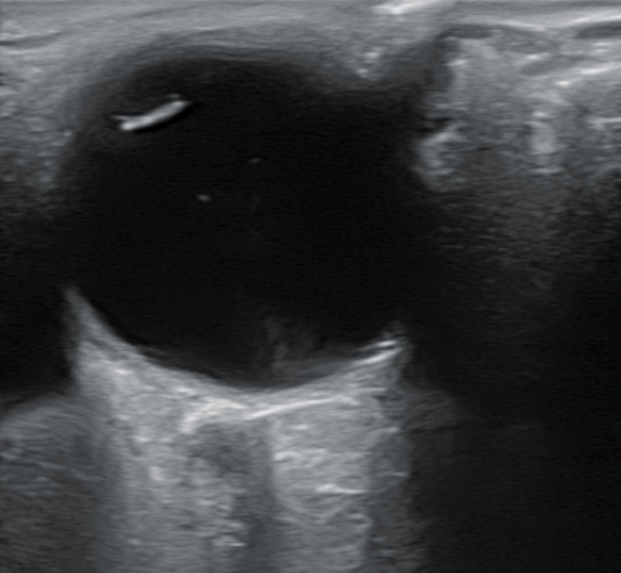

Hallazgos ecográficos

Se realiza ecografía donde se aprecia DVP en ojo derecho sin descartar hemovitreo y en campo superior y nasal una membrana más gruesa.

Se decide derivar al paciente al Servicio de Urgencias Hospitalarias para ser valorado por oftalmólogo y descartar posible desprendimiento de retina en ojo derecho. En el Servicio de Urgencias el paciente es valorado por oftálmologo de guardia y se confirma desgarro retiniano en herradura con hemovítreo.